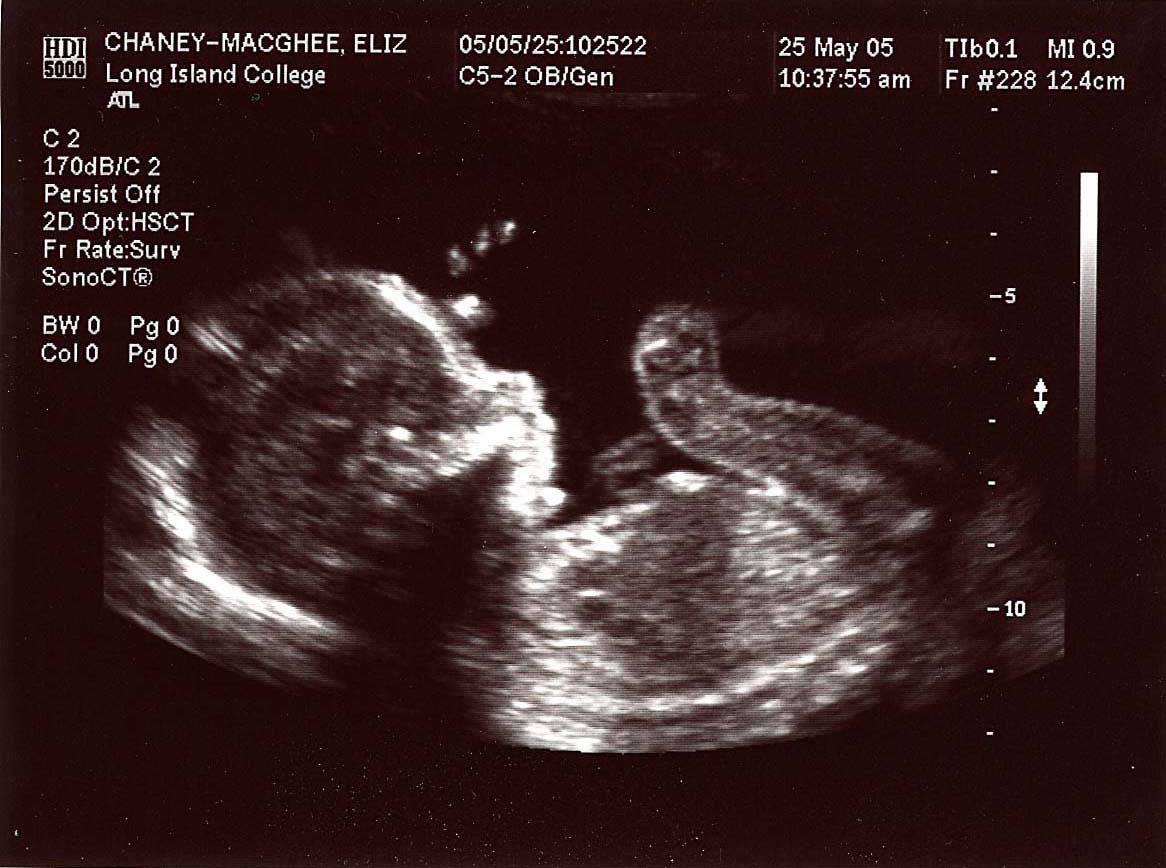

20 week series:

images taken 5/25/04, baby's weight estimated at 12 oz.

Close up, profile; 20 weeks.